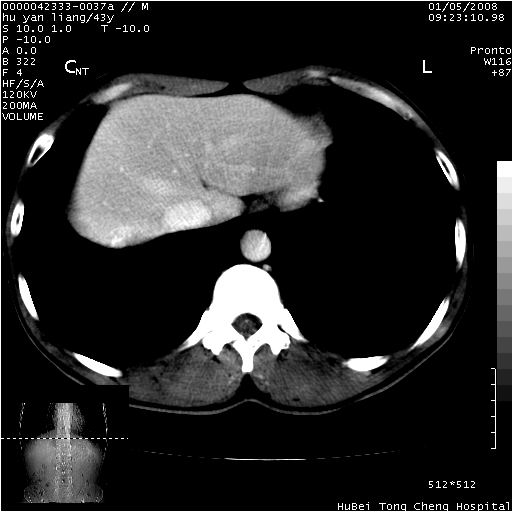

患者 男,43岁。右上腹不适1年余。既往有“肝右叶肝脓肿”病史,经保守治疗后痊愈。

b超提示:1)肝右叶肝内胆管结石。2)肝右叶占位性病变待排。

上中腹部ct轴位平扫+增强扫描(层厚10mm,螺距1.0,重建间隔10mm),图像如下:

肝右上叶偏后方较大团片状钙化灶,支持:肝脓肿后遗改变!